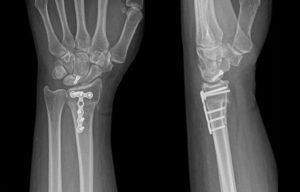

A multidisciplinary tumor board, including specialists from orthopedics, pathology, oncology, and radiology, reviewed the case and recommended surgical decompression of the spinal cord. The patient underwent posterior decompression at L5, pedicle screw fixation at L3, L4, S1, and iliac screw fixation at S2 level. She tolerated the procedure well, and her post-operative course was uneventful. Intravenous zoledronic acid was administered in the post-operative period. Wound inspection during follow-up revealed a clean and healthy surgical site (Fig. 5).

Figure 5: Post-operative radiographs (a) anteroposterior, (b) lateral views.